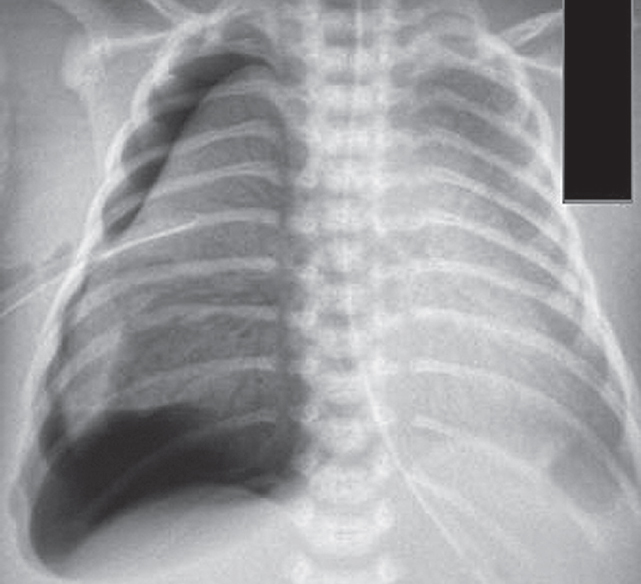

The article presents a case of successful treatment of acute respiratory distress syndrome in a full-term newborn complicated by pulmonary barotrauma using monobronchial administration of exogenous surfactant under X-ray control. In order to assess the course of the disease and the effectiveness of treatment, a retrospective analysis of medical documentation was carried out. From the first minutes of life, the child had respiratory disorders, which was the basis for non-invasive mechanical lung ventilation — nCPAP (nasal continuous positive airway pressure). Progression of hypercapnia and hypoxemia was revealed over time, and therefore tracheal intubation was performed and convective mechanical ventilation was started with FiO2 = 1,0. Monobronchial administration of exogenous surfactant was a key element of the therapy that allowed to achieve stabilization of the condition and regression of gas exchange disorders with complete recovery of the patient.

Monobronchial administration of surfactant in acute respiratory distress syndrome with heterogeneous lung involvement is an effective treatment option and can be used in clinical practice for refractory hypoxemia.